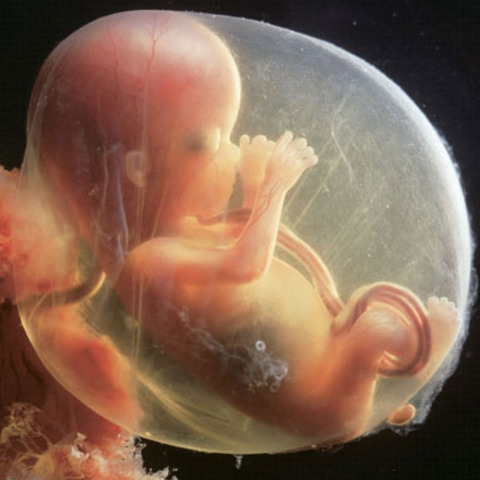

• week 9 of the fetal development

week 9 of the fetal development

the face and it's features are well formed. The head makes up nearly half of the fetus' size. Tooth buds appear.